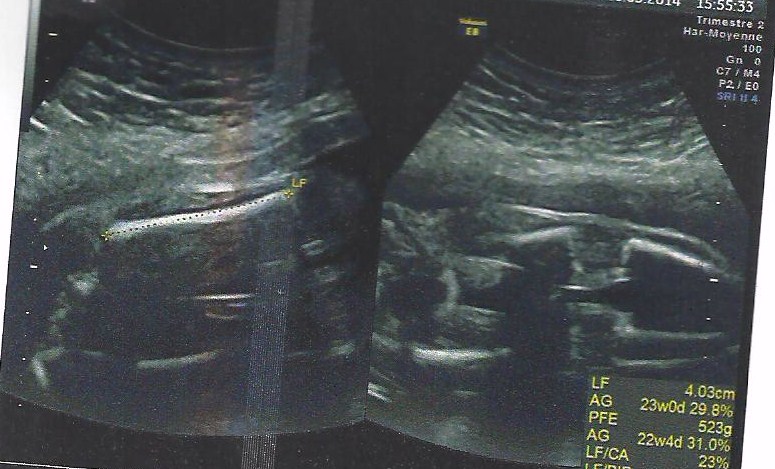

I don't think these are typical potty shots they look more like femur measurent and bladder shots. Congratulations on baby though xx

thanks , you are right these are not potty shots to show gender , but femur measurment and tibia ...

just thought people could have a guess on gender , we are not finding out till the birth ! all guesses are very welcome .